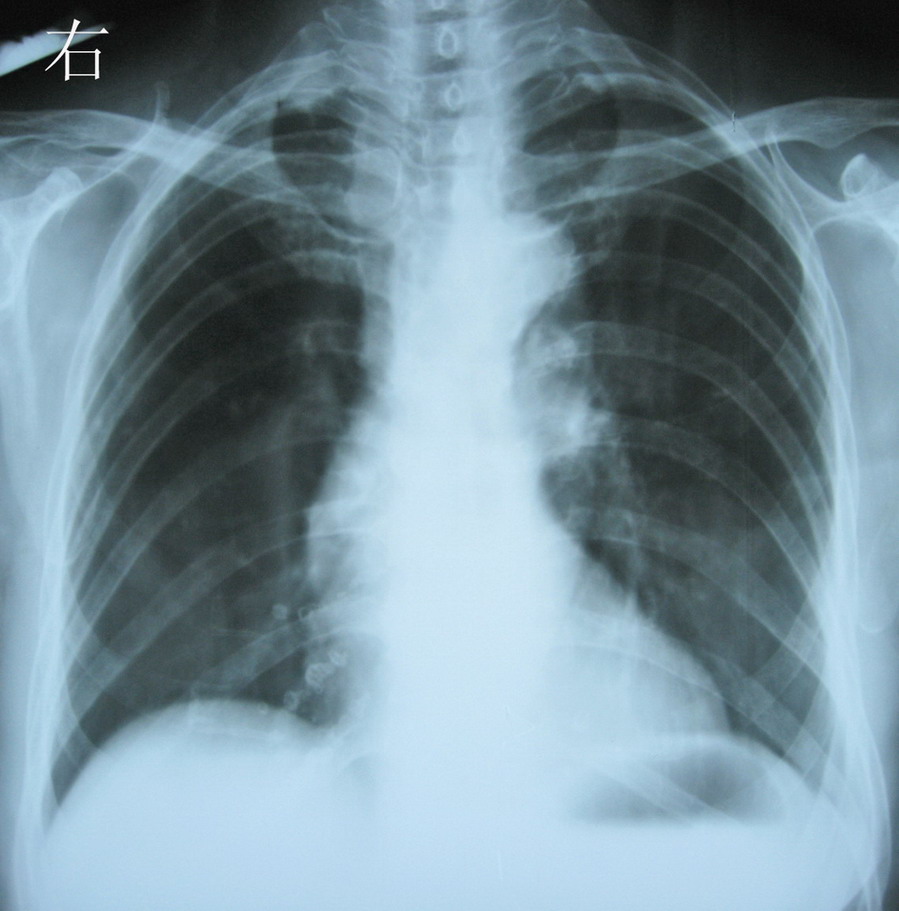

女,79,反复咳嗽10年,胸闷2年。请问有无肺心病,

两肺野透光度增强。左中下肺野见片状密度增高影,密度均匀,边缘模糊。心影形态、大小未见异常。双膈面清晰,双侧助膈角锐利。不支持肺心病,结合病史考虑:慢支并肺部感染。

慢支、肺气肿、主动脉型心影,右下钙化灶。

不支持肺心病 :肺部慢性病变不明显。心:右心无明显改变,肺动脉无高压。

慢支,肺气肿

慢性支气管炎,肺气肿征象。